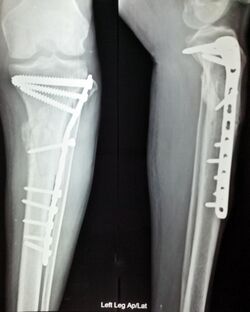

Anterior and lateral view x-rays of fractured left leg with internal fixation after surgery

Surgery is considered to be a last option when more conservative approaches fail to alleviate symptoms. Techniques such as bunionectomies may be used to surgically remove bunions and other foot and ankle deformalities, arthrodesis (or fusion of joint spaces) for inflammatory processes, and surgical reconstruction (i.e. invasive measures of manipulating neuromusculoskeletal structures) to treat other deformalities. Orthotics, physical therapy, NSAIDs, DMARDs and a change of shoe may act as a complement to surgical intervention, and in most cases will be required for optimal recovery.